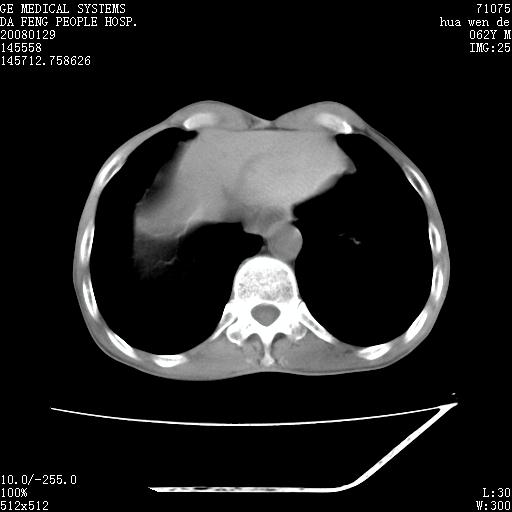

男性,67岁。作肺部检查时发现

右肺脓肿 胸腔胃

考虑:胸腔胃并支气管瘘(并发肺炎,肺脓肿形成)。

理由:1、右上肺内病灶,空洞形成,有液平。

2、肺内多处炎症。

3、前段肺内炎症,支气管引流通畅,与肿块无关系。

考虑:胸腔胃并支气管瘘(并发吸入肺炎,肺脓肿形成)。

1.整个食管扩张,未见明显占位性病变,贲门区亦未见明显占位病变,考虑:贲门失驰缓症;

2.右上肺病变边缘可见毛刺,囊壁厚度不均匀,周围境界较清楚,未见炎性渗出性影,右上肺外带可见片状影,边缘不清,考虑:肺癌伴空洞形成、右上肺炎。

食管全程扩张,壁均匀不厚,喷门失弛缓症

右上肺空洞可见液平,临近肺野磨玻璃密度,考虑1.结核2.脓肿